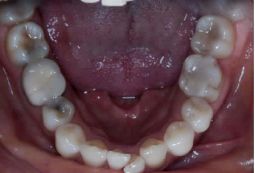

保定装置(下顎前歯固定・他取り外し式)

2年経過しても後戻りしていないことを確認。

治療前

治療後

治療後2年